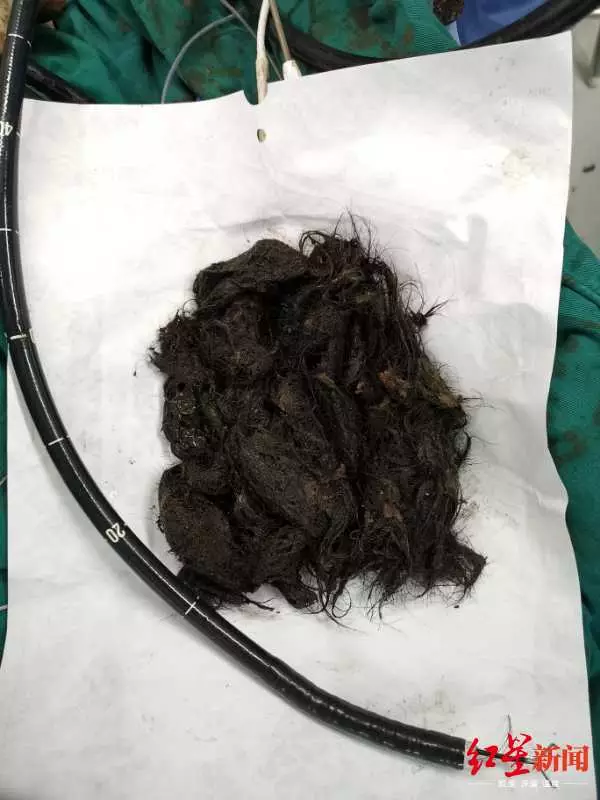

讓點點嘔吐多日的原因,竟然是因為從小吃頭髮的習慣,導致點點胃裏堆積纏繞了大量頭髮並引起了胃腸道梗阻癥狀。為了避免開腹手術給孩子帶來的巨大創傷,四川大學華西醫院消化內科、小兒外科、麻醉科、手術室等多學科醫護緊密合作,歷時近15個小時,通過內鏡手術將點點胃內的大量頭髮順利取出。

點點胃裏取出的頭髮

最終,經過消化內科、小兒外科、麻醉科和手術室醫務人員長達15個小時的通力合作,點點胃腔里的大量頭髮都通過內鏡取出來了。